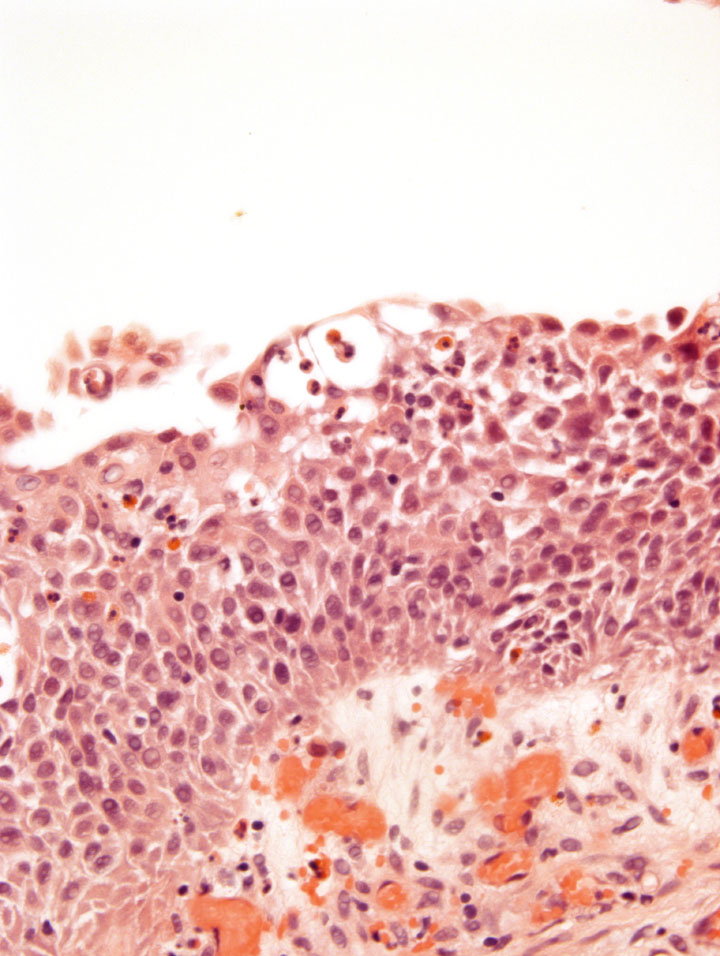

Bladder Flat Lesions

Case ID: 211

Reactive atypia

Atypia/dysplasia

Carcinoma in situ (CIS)